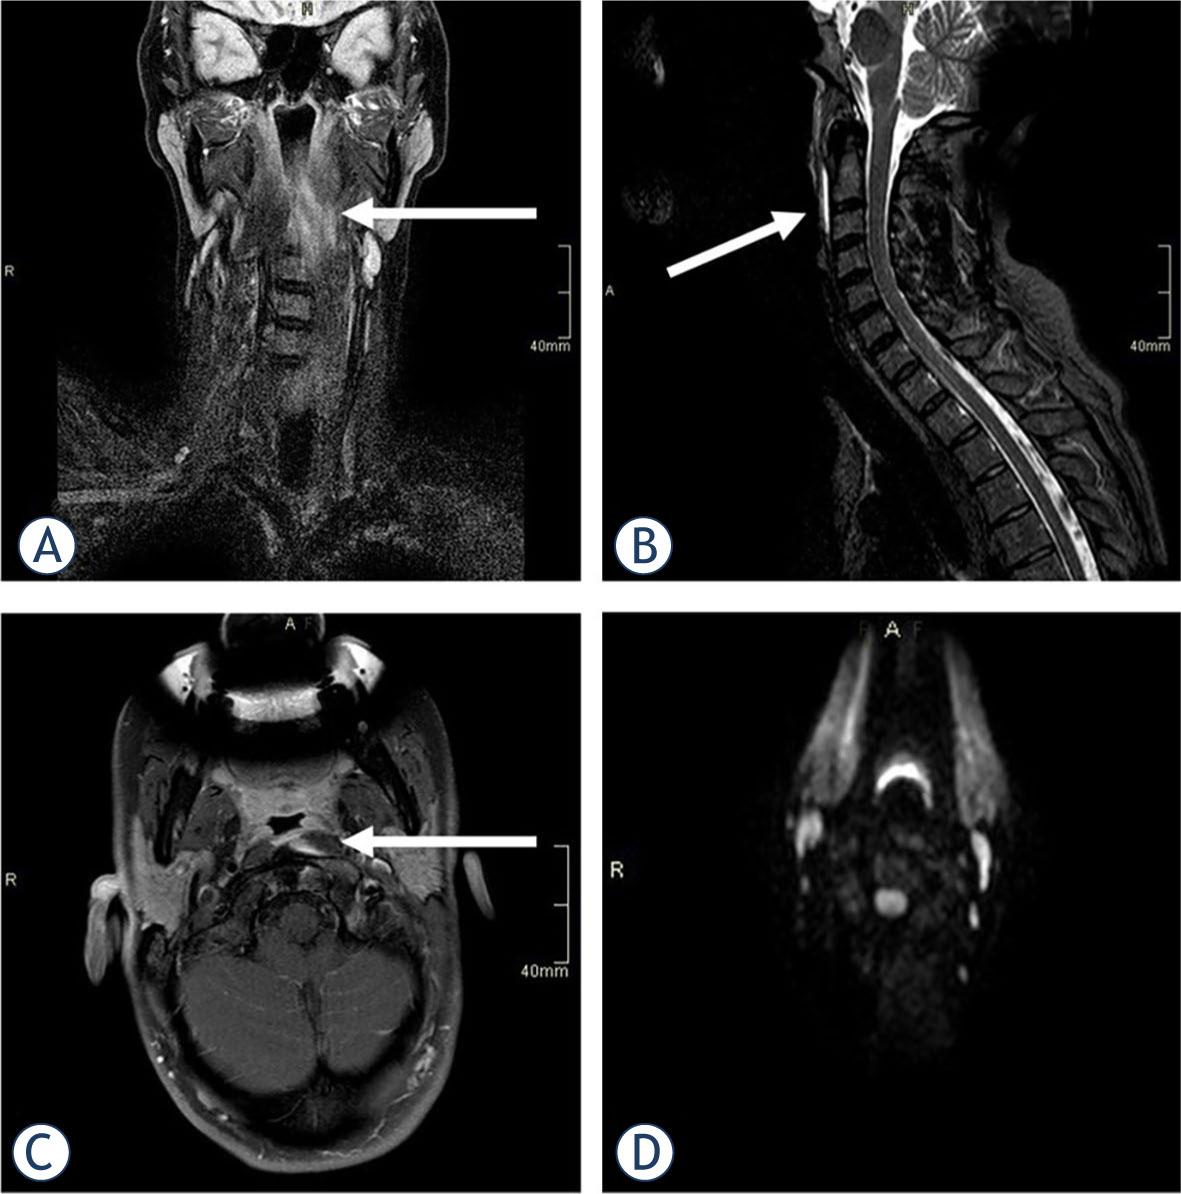

A 51-year-old female with a history of arterial hypertension was referred to the NEU in November 2021 with clinical suspicion of meningitis. Five days prior to referral, she experienced a sudden mild pain in the right posterior neck, radiating to the occipital region. In the following three days, the pain became unbearable. It increased during swallowing and with eye movements. Due to the chronic neck pain, the patient had an MRI of the neck 9 months prior to the examination. Broad-based protrusions of the C5/6 and C6/7 intervertebral discs without compromise of neural structures were described, but no other abnormalities were noted at the time. She was afebrile at presentation. A neurological exam showed limited mobility of the neck and reduced light touch sense over the right lower extremity.

Laboratory workup was normal. Head CT and computed tomography angiography (CTA) of the aortocervical and intracranial vessels revealed no vascular abnormalities. MRI of the cervical spine revealed prevertebral oedema from the C1 to the C4 level (Figure 2), not seen on previous MRIs. In addition, calcifications in front of the C1 arc on CTA was noted. The patient had been treated three days in the hospital and discharged with ibuprofen, 1800 mg daily. The pain gradually subsided over the next two months. The sensory disturbance over the left leg remained unexplained.

STIR (short tau inversion recovery) imaging in sagittal (A) and axial (B) plane demonstrated prevertebral soft tissue swelling and oedema in a 51-year-old female, suggesting retropharyngeal calcific tendinitis as the underlying cause. Calcifications in the medial aspect of the longus colli muscle in front of the C1 arc were noted on computed tomography angiography (CTA) (C), confirming the diagnosis.